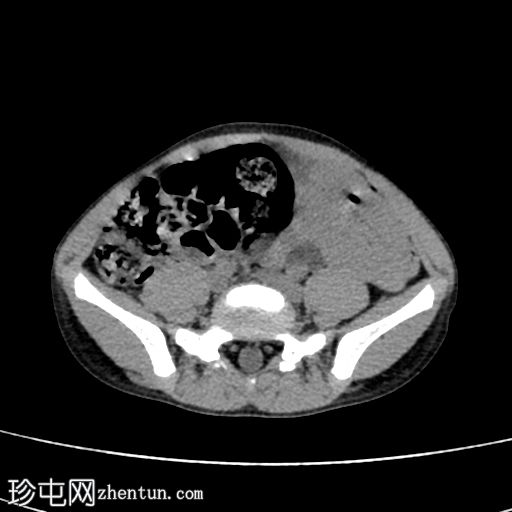

冠状位增强CT(延迟期)

在这张多期增强CT图像中,我们可以观察到肾盏、肾盂以及左侧输尿管全程扩张。

未见感染或其他相关征象。

本例为原发性巨输尿管。整个泌尿系统的扩张是诊断的关键。

超声、CT或MRI均可诊断。

巨输尿管分为两种类型:

原发性巨输尿管,由输尿管膀胱连接处的功能性或解剖性异常引起。原发性巨输尿管进一步细分为四种类型: